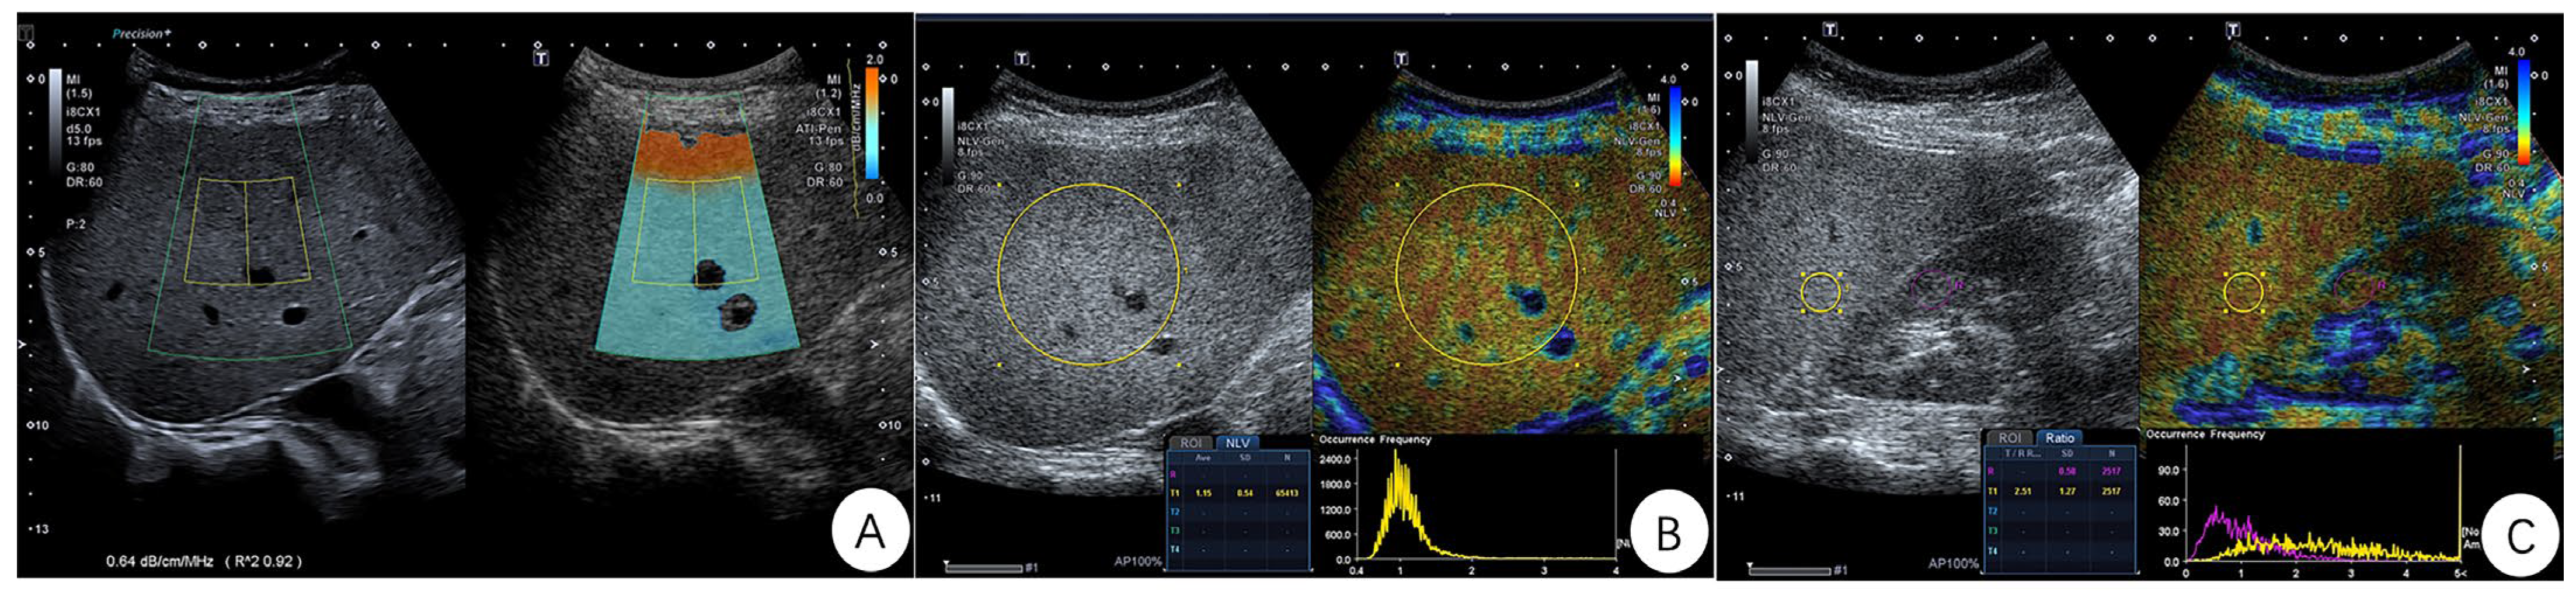

Figure 1.

Representative images of the ATI, NLV, and Ratio examination in one patient. (A) ATI image: The ultrasound (US) image is shown on the left and the same US image overlaid with the attenuation map is shown on the right. The attenuation coefficient (AC) is shown to be 0.64 dB/cm/MHz, and the coefficient of determination (R2) is 0.92. (B) NLV image: A 50 mm ROI is placed in the liver parenchyma and 10 mm below the liver capsule. The average value (Ave) of NLV is 1.15 and the standard deviation (SD) is 0.54. (C) Ratio image: A 10 mm circular ROI is free of vessels or artifacts within the liver parenchyma, and a 10 mm circular ROI is placed within the right kidney cortex which is free of fat, large vessels and renal pyramids. The liver–kidney intensity ratio (Ratio) of 2.51 and SD of 1.27 are displayed at the bottom of the image.